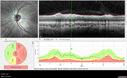

25 year old with AD optic atrophy. VA 20/80 OU. Her father also had vision loss and optic atrophy.

Autosomal Dominant Optic Atrophy - OPA1 Mutation145 views25 year old female with VA 20/80 OU and recent vision decline. Her father also has poor vision.00000

Autosomal Dominant Optic Atrophy - OPA1 Mutation163 views25 year old female with VA 20/80 OU and recent vision decline. Her father also has poor vision.00000

Autosomal Dominant Optic Atrophy - OPA1 Mutation161 views25 year old female with VA 20/80 OU and recent vision decline. Her father also has poor vision.00000